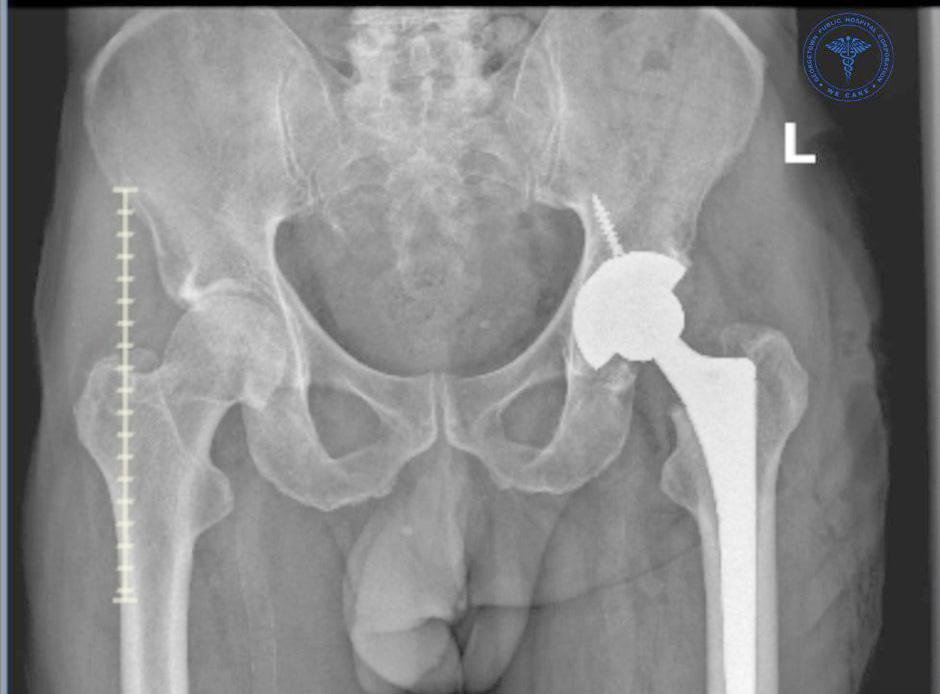

IN a significant move to reduce the growing backlog of joint replacement surgeries, the Orthopaedics Department at the Georgetown Public Hospital Corporation (GPHC) conducted a series of knee and hip replacement surgeries over the weekend.

According to a press release, a total of 12 joint replacement procedures were successfully completed: eight knee replacements and four hip replacements, marking a notable boost in the department’s surgical output.

Typically, only emergency surgeries are performed on weekends at GPHC, and joint replacement surgeries are limited to two per week, as operating theatre time is shared among multiple de-

partments.

However, to address the long list of patients awaiting care, the Orthopaedics Department has been dedicating one weekend each quarter to perform additional surgeries.

Among the 12 procedures done this past weekend, four were same-day surgeries, where patients were admitted on the morning of the operation and discharged by evening.

This is a relatively new initiative at GPHC, with the first same-day joint replacement having been completed in March 2025.

The success of this approach is a testament to the advanced surgical techniques and enhanced recovery protocols now being implemented by the department’s

skilled surgical team.

The remaining eight patients were discharged within 24 hours, further demonstrating the team’s commitment to improving patient outcomes and hospital efficiency through modern, minimally invasive practices.

To date, the Orthopaedics Department has completed a total of 79 joint replacement surgeries for the year, reflecting the dedication and ongoing efforts of the team to meet the needs of patients awaiting life-changing procedures.

Joint replacement surgery is typically recom -

mended for individuals experiencing severe joint pain, stiffness, or mobility issues—most commonly in the knees or hips—that significantly affect their quality of life.

These symptoms are often caused by osteoarthritis, rheumatoid arthritis, traumatic injury, or other degenerative joint diseases.

When other forms of treatment such as medication, physical therapy, or lifestyle modifications no longer provide relief, joint replacement surgery may be considered as a last resort to restore mobility and

reduce pain.